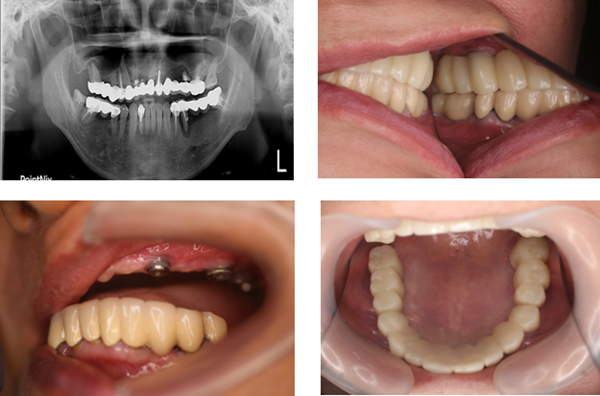

其實我在還沒去看牙醫之前,根本就不知道自己的牙齒事需要做到全瓷冠假牙補牙的地步,但直到照完X光片後,才意識到這顆蛀牙的狀況好像真的有點嚴重。牙醫師通常會依照患者牙齒缺損程度給予不同的治療,當蛀洞範圍較小時會使用樹脂填補,也就是大家所知道的補牙。而當牙質損壞程度太嚴重時,則會以全瓷冠牙套對缺牙進行修補。

陳奕安醫師耐心的和我解說全瓷冠假牙不僅可以締造仿若真牙的逼真感,硬度也較從前的假牙材質好許多,可一併矯正牙齒因根管治療變黑情況,與自身牙齒太過於脆弱的困擾,令牙齒咬合變得更正常。

在做全瓷冠假牙補牙這部分過程須經清除蛀牙的部分>牙齒壓模>挑選牙模顏色>全瓷冠齒模修型>黏上你蛀牙的缺洞,即便現在看來就是簡單的這五步驟,但陳奕安醫師在治療我的每個步驟不但都做得很細心謹慎外,也都時刻關心安撫著我緊張不安情緒~做牙套療程時間很快大約只需要3-5周左右就可以完成((以上須視個人情況時間長短不一))